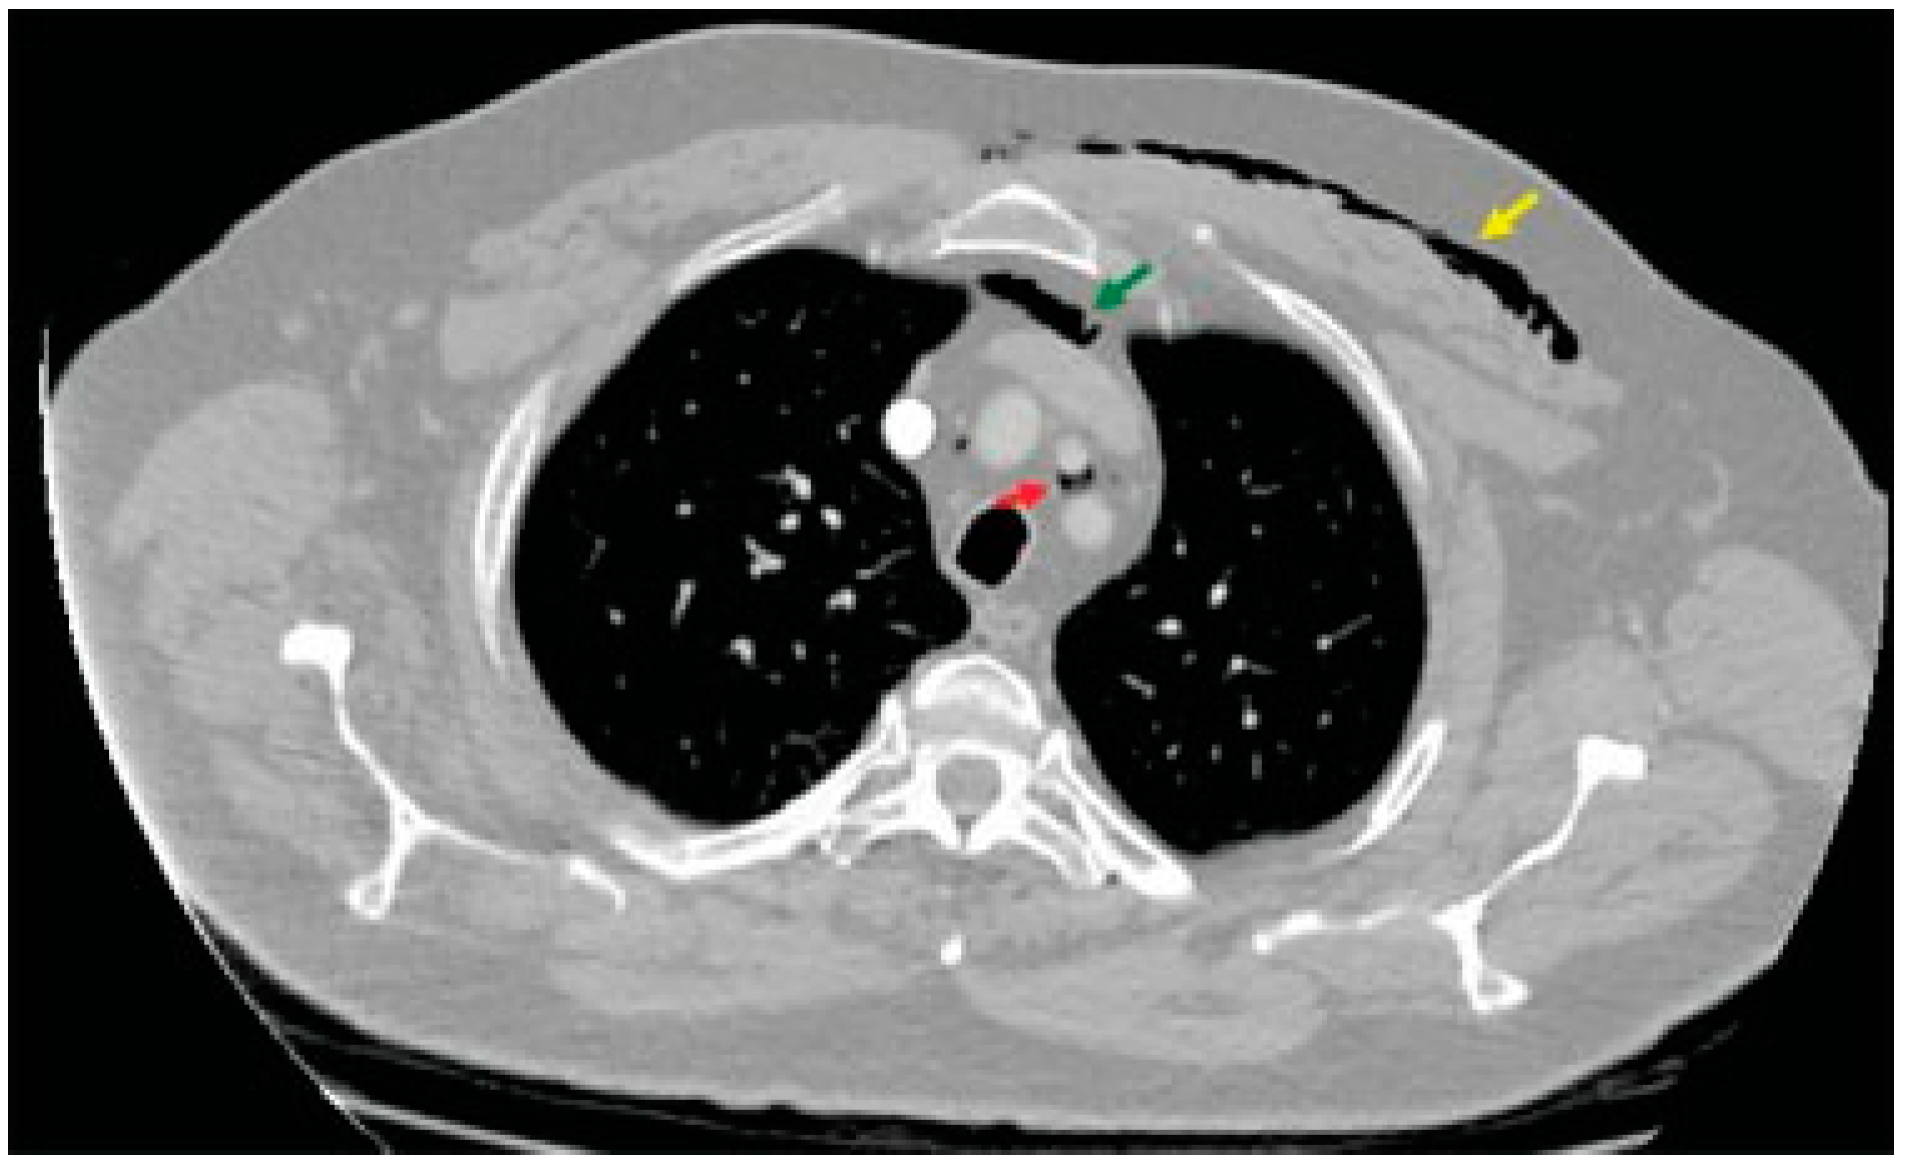

Routine blood tests, arterial blood gases, electrocardiography, and cardiac enzymes did not reveal any discrepancy. The anteroposterior and lateral views of plain radiographs of the neck showed scattered and lucent streaks owing to the presence of free air (Figure 1). Full-body computed tomo-graphic (CT) scan documented a nondisplaced fracture of right anterior sinus wall extending to the base of frontal process of ipsilateral maxillary bone (Figure 2a). Besides, it demonstrated pneumo-orbitus and massive emphysema that either occupied or extended to the following spaces: right temporal, bilateral buccal, bilateral parapharyngeal, bilateral carotid, retropharyngeal, prevertebral, visceral, anterior neck, and right posterior cervical (Figure 2b,c). The air had also spread to subcutaneous tissue of the left anterior chest wall and to the superior mediastinum, both retrosternally and between left common carotid and subclavian artery (Figure 3 and Figure 4). Neither thoracic CT nor chest plain radiographs evidenced signs of rib or clavicle fracture.

Figure 3.

The air collections within the subcutaneous tissue of the left anterior chest wall (yellow arrow), behind the sternum (green arrow), and between the left common carotid and subclavian artery (red arrow) in transverse view.